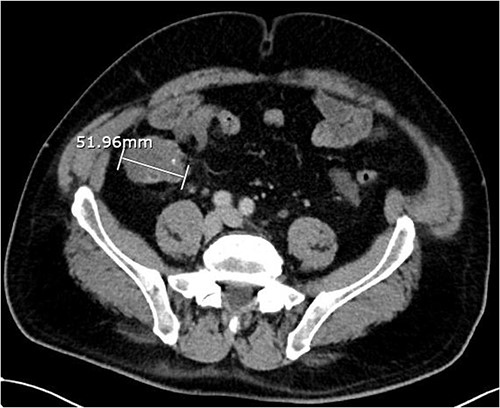

About 1 year later, the patient re-presented for anaemia and underwent a further CT scan. In the right iliac fossa, a 51.96 mm mass was noted such that the appendix could not be visualized separately, with a focus of calcification (Fig. 1). There was infiltration into the adjacent fat and abnormal soft tissue thickening of the peritoneal reflection along the right paracolic gutter. Multiple new peritoneal nodules in the upper abdomen were also identified (Fig. 2). The appearances were in keeping with disseminated malignancy. Following histological analysis, diagnoses of LAMN and PMP was made. The patient was initiated on mitomycin and capecitabine chemotherapy, which modestly reduced the size of the right iliac fossa mass from 51.96 mm to 44.23 mm (Fig. 3).

Axial CT abdomen with contrast demonstrating an appendiceal mass of maximum diameter 51.96 mm.